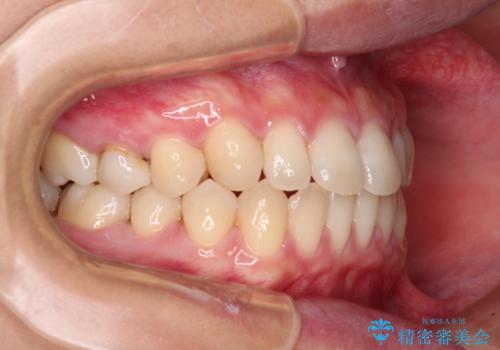

隙間だらけの歯列 インビザラインで改善

- 前歯の上下スペースと前歯の隙間を気にして来院された患者様です。

飲み込みや話をするときに舌を突出させる癖が強くあり、それが原因でスペースが空いていました。

舌癖を改善するためのトレーニングを行いながら、インビザラインにより上下の前歯の隙間を閉じていくこととしました。